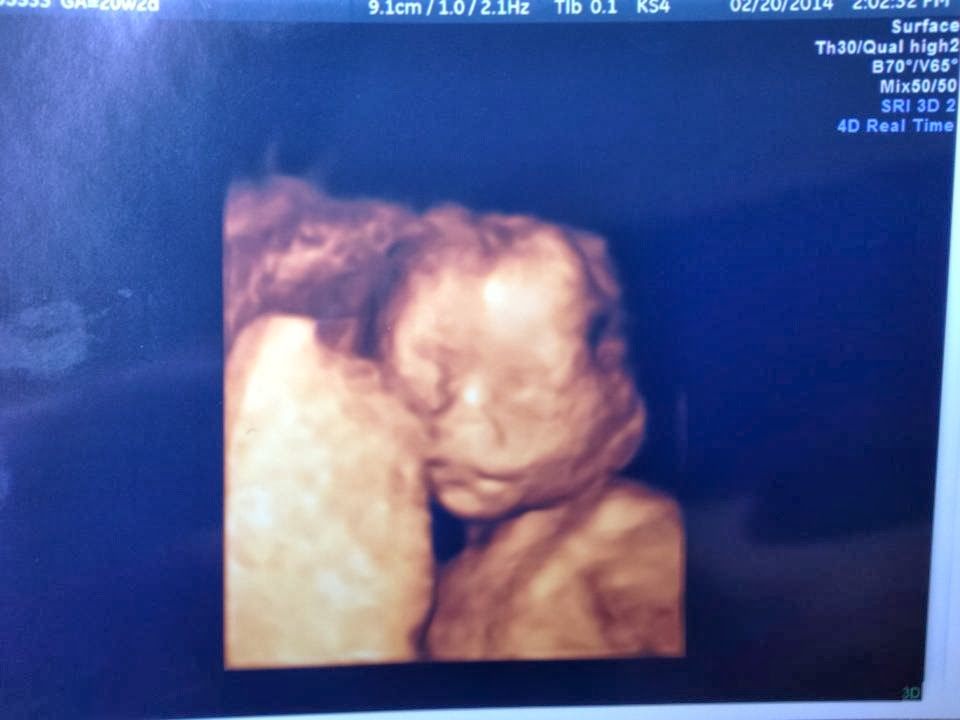

Thursday - This was the BIG DAY!!!! Anatomy scan day! Brian, Bell, Adam, and I, all met up for lunch first. I can't believe it's been a year since I saw Adam. Crazy! It was great getting us all together again. They're so fun to hang out with and they loved the Doghouse Grill we took them to. Yum! Afterwards I hitched a ride with Belle and Adam and we headed to the hospital to give Adam a mini tour. We just looked at the grounds, lobby, and cafeteria, but he thought it looked really nice and brand new. After that we swung by Best Buy really quick and then headed downtown for the ultrasound. The highlight of the day! Unfortunately we didn't think to load me up with sugar before hand so baby would be awake, but we still got a good view of their sleepy baby. Everything looked great and healthy. Heart rate was 144, estimated weight was about 12 ounces, and age based on size was about 20 weeks 1 day (measuring 4 days ahead). We even got a few 3D views while there. It was a bit difficult since baby was using the placenta as a pillow, but we finally got around it and got a few good shots. Yay! Adam stuck to his guns and held out on finding out the sex, so it looks like we'll be waiting till birth as planned... unless he caves before then. Later that night we all met up again for dinner. Linc didn't make it since it was pretty late, but the girls did. They were shy at first meeting Adam for the first time, but after about 5 minutes they were back to their crazy selves. Haha! We even got a few family pics in before they left.

| Baby resting their head against the placenta while sleeping. |